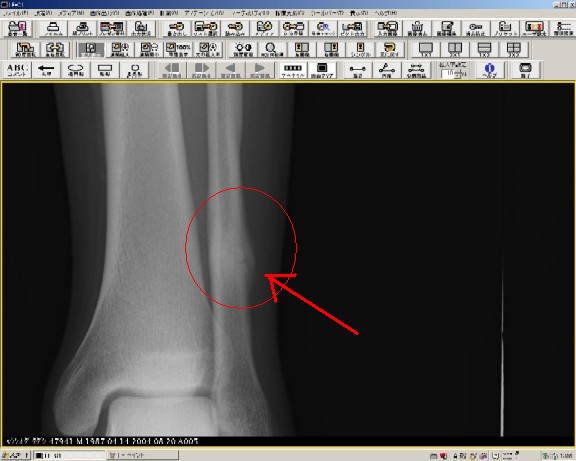

| 1、バレーボール三年目の高1の選手。左足首捻挫から一ヵ月後に腓骨骨折判明した。 |

腓骨遠位端部(ふくらはぎ外側足首に近い方)に圧痛があり、レントゲン船線像にて骨膜の肥厚が見られる。

(疲労骨折) |

より拡大像にて肥厚した部分(仮骨(Callus))が鮮明に写し出されます。 |